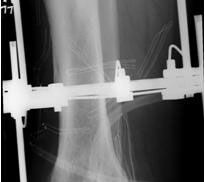

• Primäre oder posttraumatische Arthrose des OSG und USG (Abbildung 1, Abbildung 2).

• Revision einer gescheiterten Fusion des OSG/ USG (Abbildung 3, Abbildung 4).